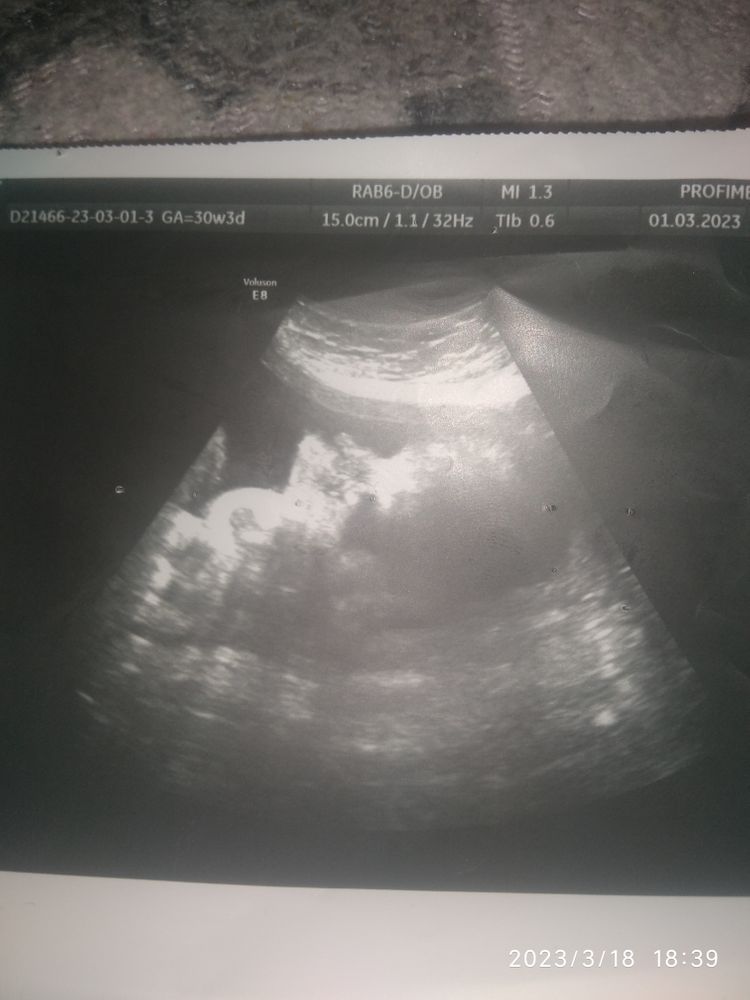

В 32 недели ещё не известен пол? 👀

Анна, пол привыкает по весу срока, типо крупный. По фото не понятно... Если бы знала, то не спрашивала кто кого видит на фото.

Екатерина , фото просто нечёткие. Вообще ничего не понятно. Вот тут мальчик, видите справа? Сидит на попе, две ножки и писюлек между ними. Изображение

Анна, да, на Вашем фото видно четко пол) А на моем... Хотя бы на первом что либо увидеть)))

Екатерина , на вашем сроке уже часто делают УЗИ, скоро узнаете, или покупайте вещи нейтральных тонов, чтобы не было сюрприза.